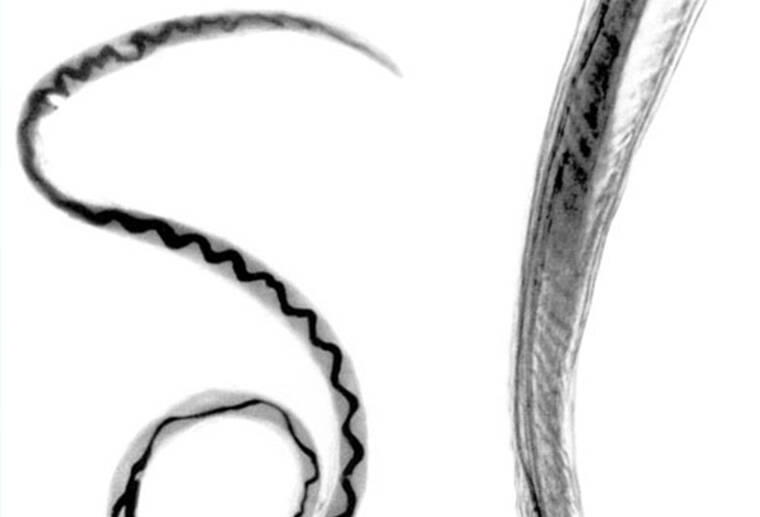

Rat lungworm disease, a parasitic disease also known as neuroangiostrongyliasis, is known to be endemic on all islands in Hawaii. The diagnosed individual had no history of travel to other islands, outside the state or country, officials said.

Rat lungworm disease , caused by a roundworm parasite call